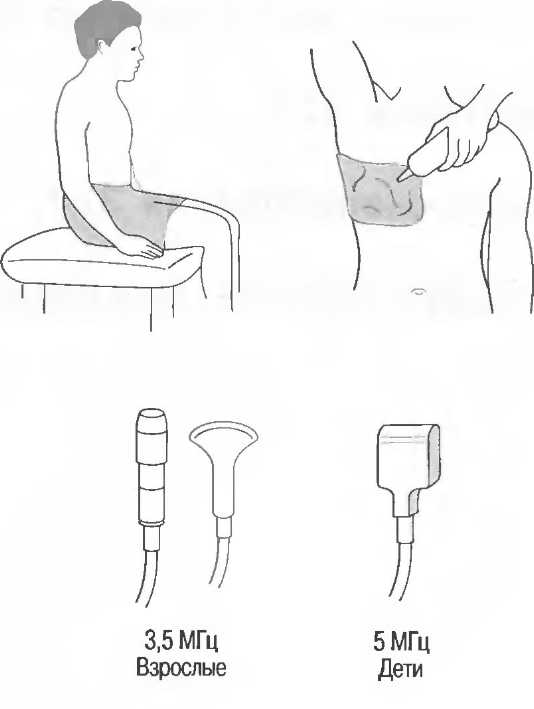

Затухание

Ткани тела поглощают и рассеивают ультразвук по-разному. Высокие частоты поглощаются и рассеиваются (гасятся) в большей степени, чем низкие. Поэтому, чтобы достичь более глубоких тканей, необходимо использовать более низкие частоты, так как менее вероятно, что эти волны затеряются при прохонодении через ткани. На практике оптимально использовать частоту около 3,5 МГц для глубокого сканирования у взрослых и частоту 5 МГц и выше для исследования более худых пациентов или детей. Частота 5 МГц и выше используется для исследования поверхностных органов у взрослых.

Выбор соответствующего датчика

Наилучшим датчиком для общей практики является конвексный датчик с частотой 3,5 МГц с фокусировкой на расстоянии 7-9 см. Если такого датчика нет, необходимо наличие линейного секторного датчика с частотой 3,5 МГц. При необходимости исследования детей и худых взрослых желательно дополнить набор датчиком с частотой 5 МГц с фокусировкой 5-7 см.

1. Ультразвуковые исследования в акушерстве. Для общих исследований в акушерстве используется линейный или конвексный датчик с частотой 3,5 или 5 МГц с глубиной фокусировки на 7-9 см. Если закупается только один датчик, выбирайте датчик с частотой 3,5 МГц. Датчик с частотой 5 МГц предпочтителен на ранних сроках беременности. В поздние сроки беременности лучше использовать датчик с частотой 3,5 МГц.

2. Ультразвуковые исследования в общей практике. Если проводятся исследования в верхней части живота и таза у взрослых, в том числе и акушерские исследования, предпочтительнее выбор секторного или конвексного датчиков с частотой 3,5 МГц с глубиной фокусировки на 7-9 см.

3. Ультразвуковые исследования в педиатрии. Для детей необходим датчик с частотой 5 МГц с глубиной фокусировки на 5-7 см. При исследовании мозга новорожденного используется секторный датчик с частотой 7,5 МГц с глубиной фокусировки на 4-5 см (этот датчик также используется для исследования яичек и структур шеи у взрослых).